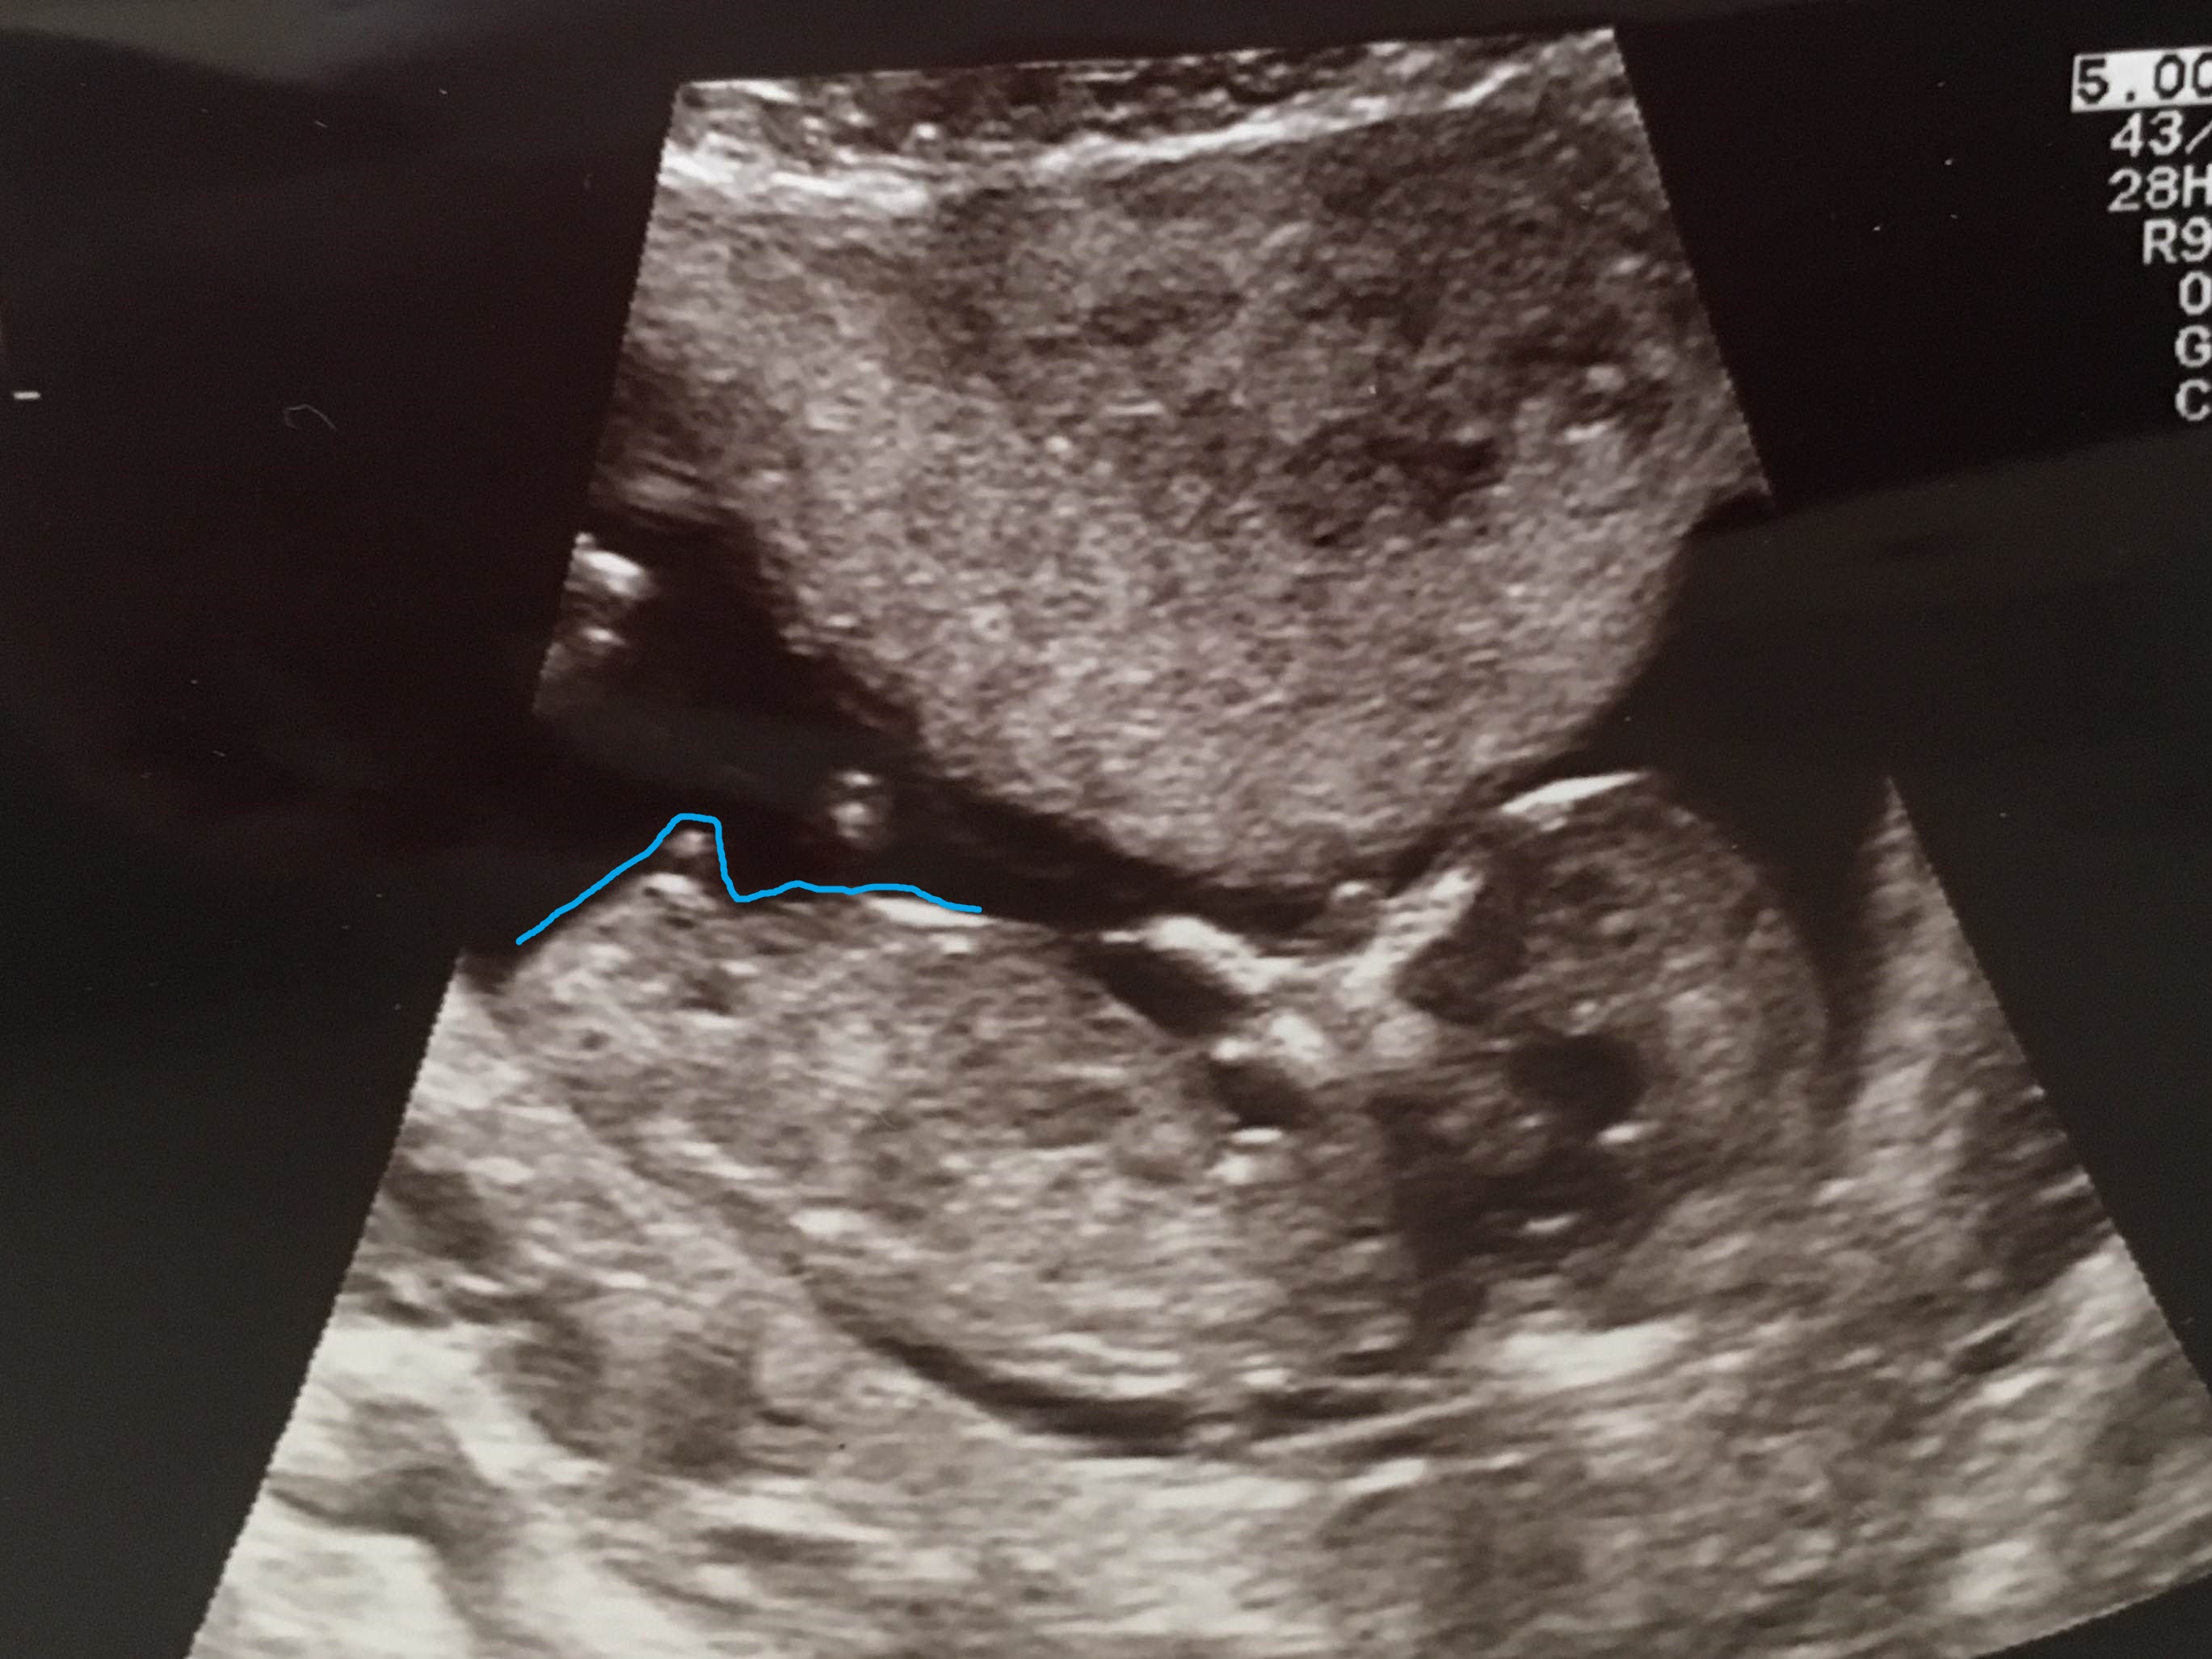

This week I had my 12w+5d scan and my doc said there was no NUB to see. So she couldn't tell me something about the gender from the NUB theory.

But what do you think? Is there a NUB to see?

BOY!!!! :DS:

Most docs and many techs don't know about nub theory, that's why. She probably didn't know what to look for or maybe even what a nub is.

Looks like a boy nub to me too :)